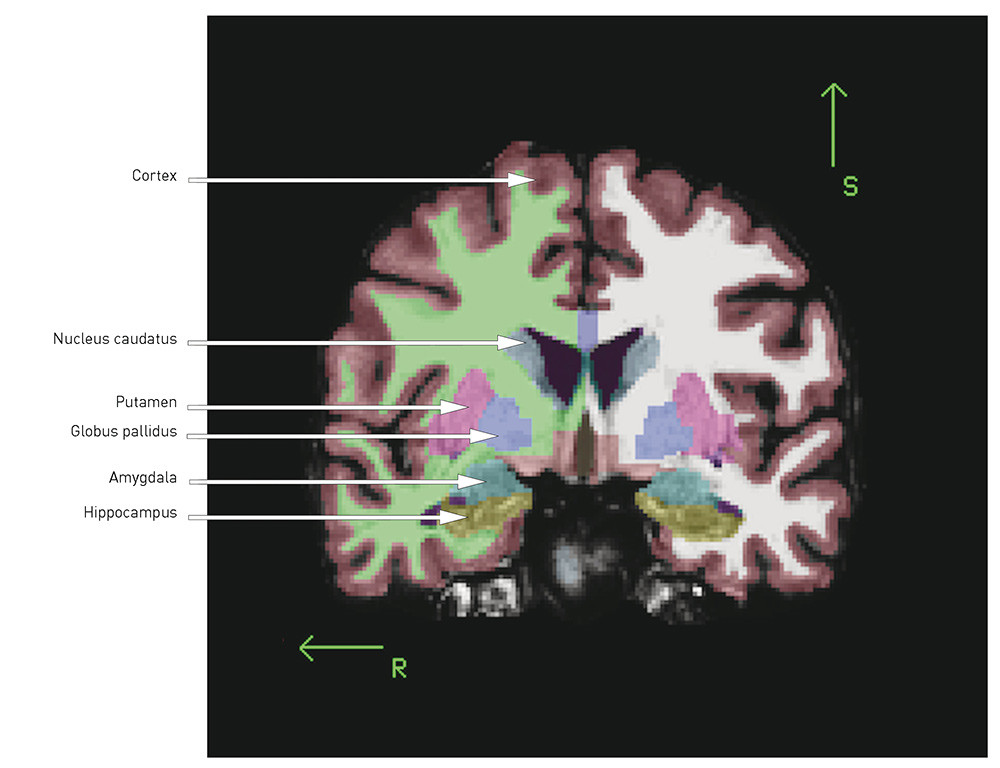

Når totalvolumet er mindre og ventriklene større, kan man spørre seg om det er visse regioner eller strukturer der volumreduksjonen er mer uttalt. Her følger en kort oversikt over de best replikerte funnene (for illustrasjon, se fig 1 og fig 2):

Hippocampus ligger medialt i temporallappen og er viktig for verbal innlæring og hukommelse. Denne er jevnt over rapportert å være mindre hos pasienter med schizofreni enn hos friske kontrollpersoner (4, 9), noe vi også har rapportert fra to skandinaviske kohorter (7, 11, 12). I en nylig publisert metaanalyse av 44 MR-studier ble effektstørrelsen funnet å være moderat (d = –   0,48 og –   0,53 for henholdsvis venstre og høyre hippocampus) (13), og det var ingen forskjell mellom førsteepisode og kronisk schizofreni. At forandringene var til stede ved sykdomsdebut, kan tyde på at hippocampusreduksjonen ved schizofreni er utviklingsrelatert. Volumreduksjonen kan representere tap av grå substans, og dette kan ha betydning for kognitive funksjoner som innlæring og hukommelse, som er vist nedsatt ved schizofreni (14).

Det er i flere studier, inkludert våre egne (7, 11, 15), og i metaanalyser (5, 16, 17) vist større volum av basalgangliene, spesielt uttalt i globus pallidus, ved schizofreni. Basalgangliene er dopaminfiberrike, og forandringer kan derfor være vanskelig å tolke siden strukturene påvirkes av antidopaminerge antipsykotika (18).

Thalamus, en midtlinjestruktur som grenser mot ventriklene, har vist seg å være mindre hos pasienter med schizofreni (19). I en metaanalyse er det vist effektstørrelse på d = –   0,32 (høyre) og d = –   0,33 (venstre) ved kronisk og d = –   0,45 (høyre) og d = –   0,48 (venstre) ved førsteepisode schizofreni (20). Thalamus fungerer som knutepunkt for hjernens kognitive prosesser, og en hypotese er at informasjonsflyten mellom ulike hjerneområder er forstyrret ved schizofreni (21).

Cortex er en innfløkt struktur med sulci og gyri. Nevronene i cortex er blant annet involvert i viljestyrte og kompliserte kognitive prosesser. De første MR-studiene påviste mindre volum av cortex, spesielt i frontal- og temporallappen (4). Volumreduksjonen er blitt replikert i flere senere studier og kan reflektere reduksjon av nevropil (umyeliniserte nerveceller, synapser og gliaceller), som vist ved nevropatologiske post mortem-studier (22). Mindre volum kan skyldes redusert tykkelse og/eller areal (volum = tykkelse x areal). I vår gruppes studie fra Oslo fant vi tynnere cortex samt mindre areal og volum ved schizofreni, der volumforandringene var «drevet» av tykkelsesreduksjonen (23). Dette stemmer overens med flere andre studier som viser tynnere cortex, mest uttalt frontalt og temporalt, ved schizofreni (24) – (26).